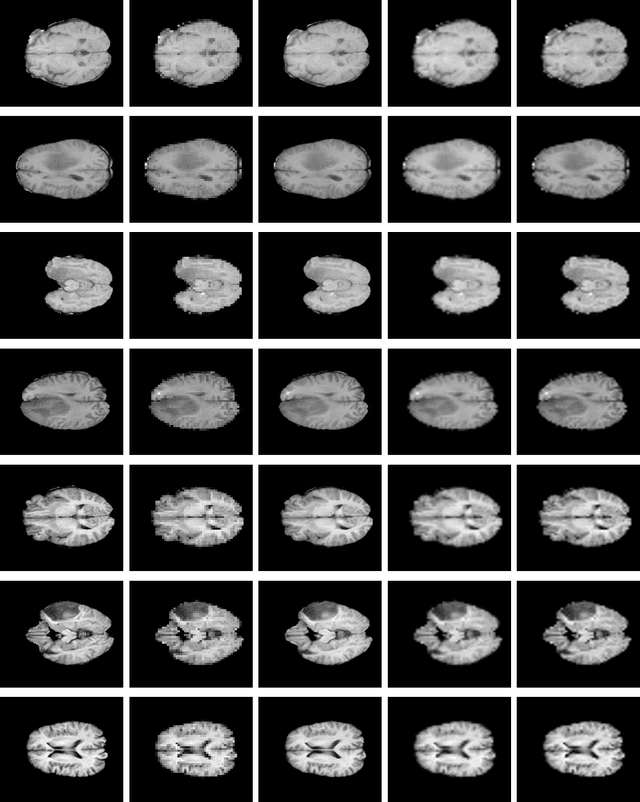

Abstract:Spatial resolution of medical images can be improved using super-resolution methods. Real Enhanced Super Resolution Generative Adversarial Network (Real-ESRGAN) is one of the recent effective approaches utilized to produce higher resolution images, given input images of lower resolution. In this paper, we apply this method to enhance the spatial resolution of 2D MR images. In our proposed approach, we slightly modify the structure of the Real-ESRGAN to train 2D Magnetic Resonance images (MRI) taken from the Brain Tumor Segmentation Challenge (BraTS) 2018 dataset. The obtained results are validated qualitatively and quantitatively by computing SSIM (Structural Similarity Index Measure), NRMSE (Normalized Root Mean Square Error), MAE (Mean Absolute Error), and VIF (Visual Information Fidelity) values.